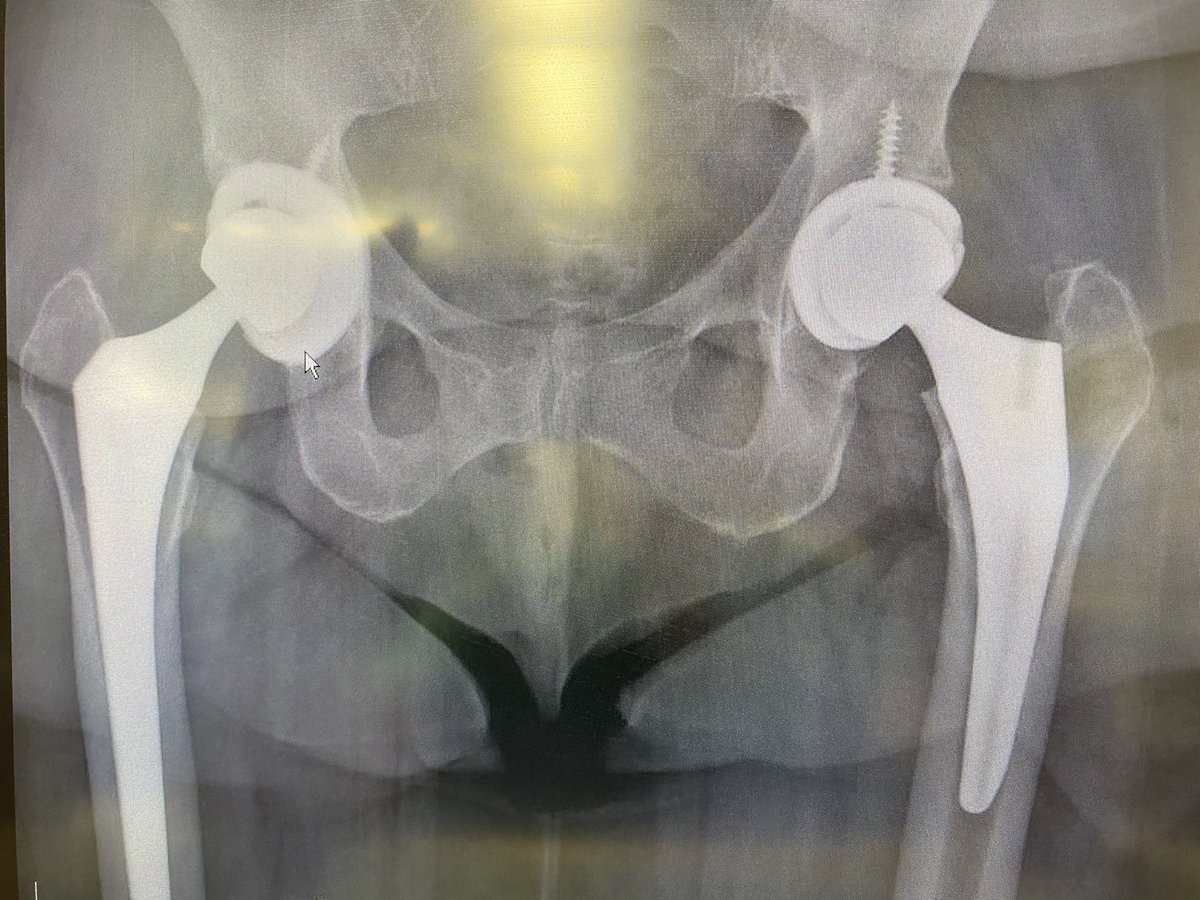

New Years brought me 2 distal femoral replacements 🤔. Not sure if that is a good sign or not, especially since I have had a lot of my revisions waiting because of COVID restrictions. 2022 may be a long year. #orthotwitter

@depurhro revised plus ORIF in my hands. In older patients I have also tended to extend fixation across the entire femur for prophylactic femur protection. Pics of recent case but press fit stem. Slightly different concepts. ?anyone else prophylactic long femur fixation?